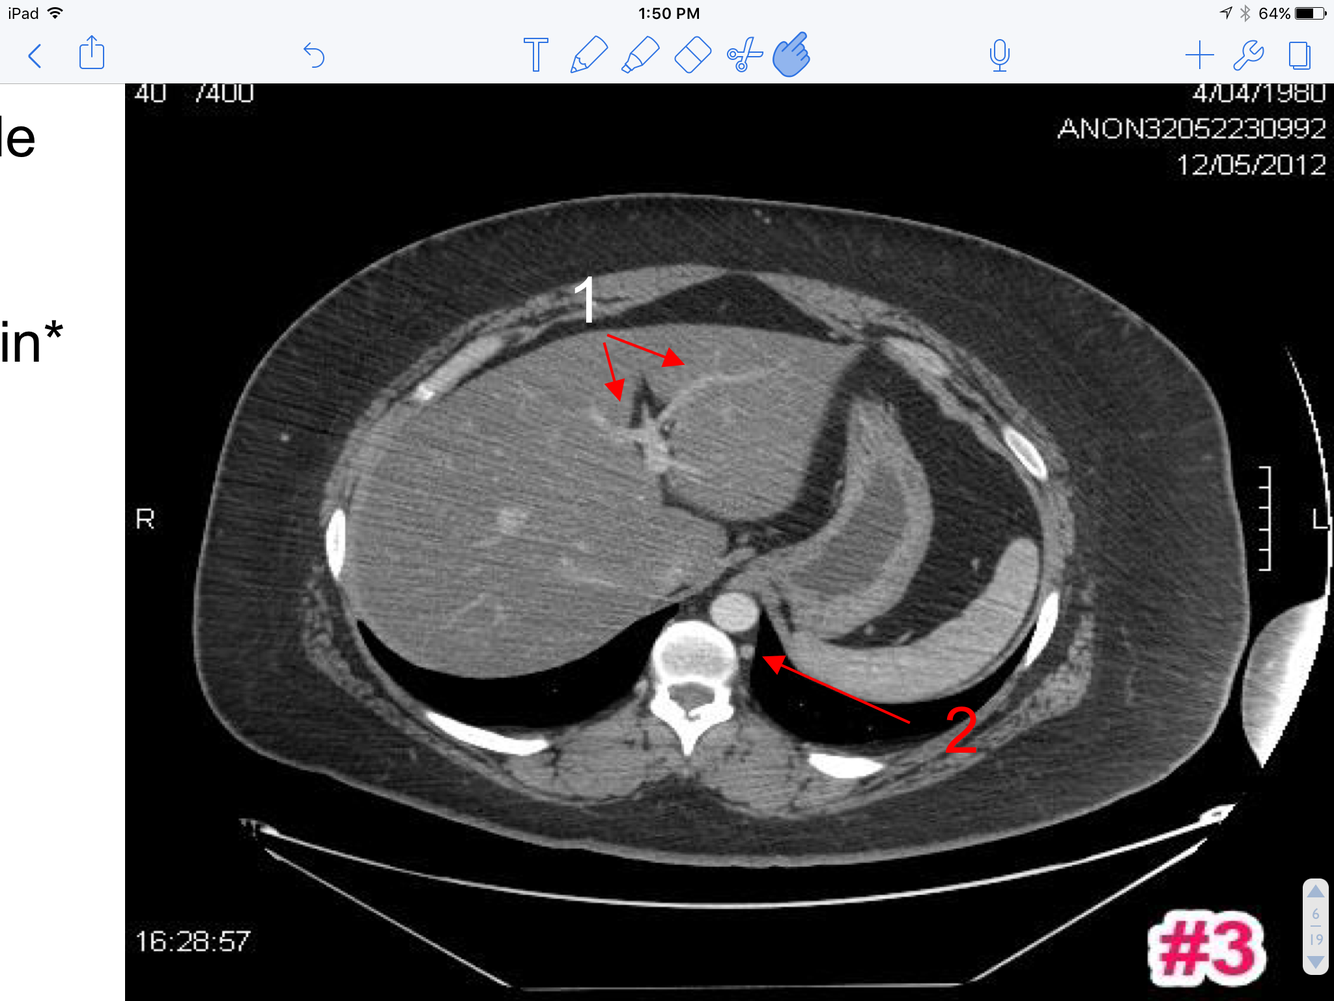

3

A

1. Branches of the Lt. branch of the portal vein

2. Hemiazygos vein